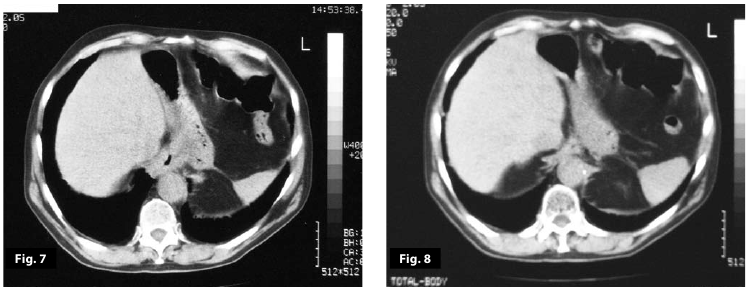

Figure7

Figure8

Figure7-8